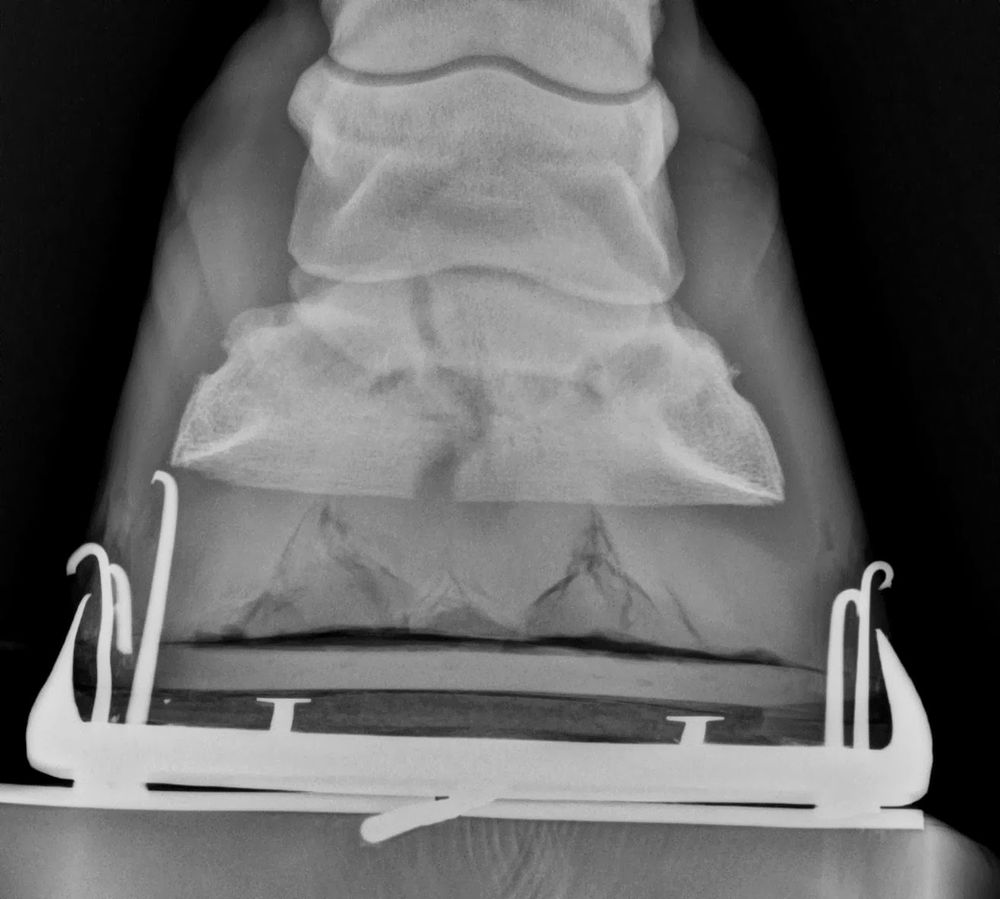

Bone spur r/Radiology Bone Spur On Coffin Bone In the very young horse, the distal phalanx correlates well with the hoof shape. Our gelding’s broken hock has healed with what the veterinarian calls bone spurs. Coffin bone fracture is a fairly common cause of lameness in horses. The signs of a coffin bone fracture are similar to such common problems as a stone bruise, abscess, or laminitis (except. Bone Spur On Coffin Bone.

From www.researchgate.net